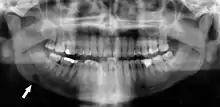

A dental panoramic radiograph, showing the maxilla and mandible, all the teeth including the "wisdom teeth," the frontal and maxillary sinuses, the nasal cavity and the temporomandibular joint and other near by head and neck anatomy.